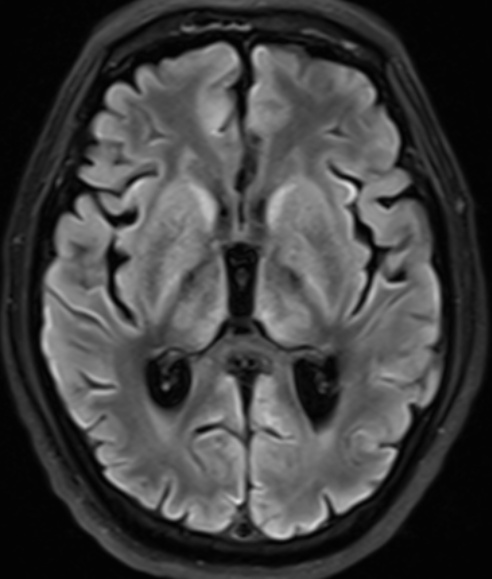

MRI病变评估方法参考既往研究中描述的方案[7]。由两位具有丰富经验的神经放射学家,在未知患者临床诊断的前提下评估双侧大脑区域病变情况,包括额叶、颞叶、顶叶、枕叶、胼胝体膝部和(或)体部、胼胝体压部、基底节区、丘脑、脑干、小脑,共计18个解剖区域。每个脑区采用二分类评分法:0分表示无病变或只有小的局灶性病变;1分表示有较大的病变(累及该脑区体积的30%以上)或弥漫性病变(图1)。

Figure 1. The T2-weighted and diffusion images of a patient

1. 一名患者的T2加权和弥散图像

患者为60岁男性,入院诊断为呼吸心跳骤停(心肺复苏术后)、脑梗死恢复期,入院时双侧瞳孔对光反射消失,图像显示两侧基底节区、丘脑弥漫性缺氧损伤,且脑干出现多发病变,患者出院时仍为植物状态。